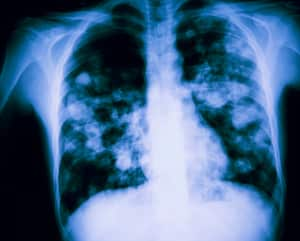

¿Cómo se puede saber si el corazón está sano?

El corazón es importante por su función de impulsar la sangre hacia los órganos, tejidos y células del organismo; además, muchos expertos lo asocian al motor de un carro, pues, gracias a su trabajo, el cuerpo y los vehículos se ponen en movimiento.

“Un corazón sano es fundamental para proveer el oxígeno y nutrientes que nuestro cuerpo necesita”, destacó la entidad. Por tal razón, dijo que una de las señales de un corazón saludable es que interactúa correctamente con los demás órganos del cuerpo, como el pulmón y el riñón, bombeando la sangre oxigenada de forma efectiva.

Cuando este proceso de conducción no se realiza correctamente, comienzan a manifestarse síntomas que pueden indicar la presencia de enfermedad cardiovascular. Algunos de estos son: